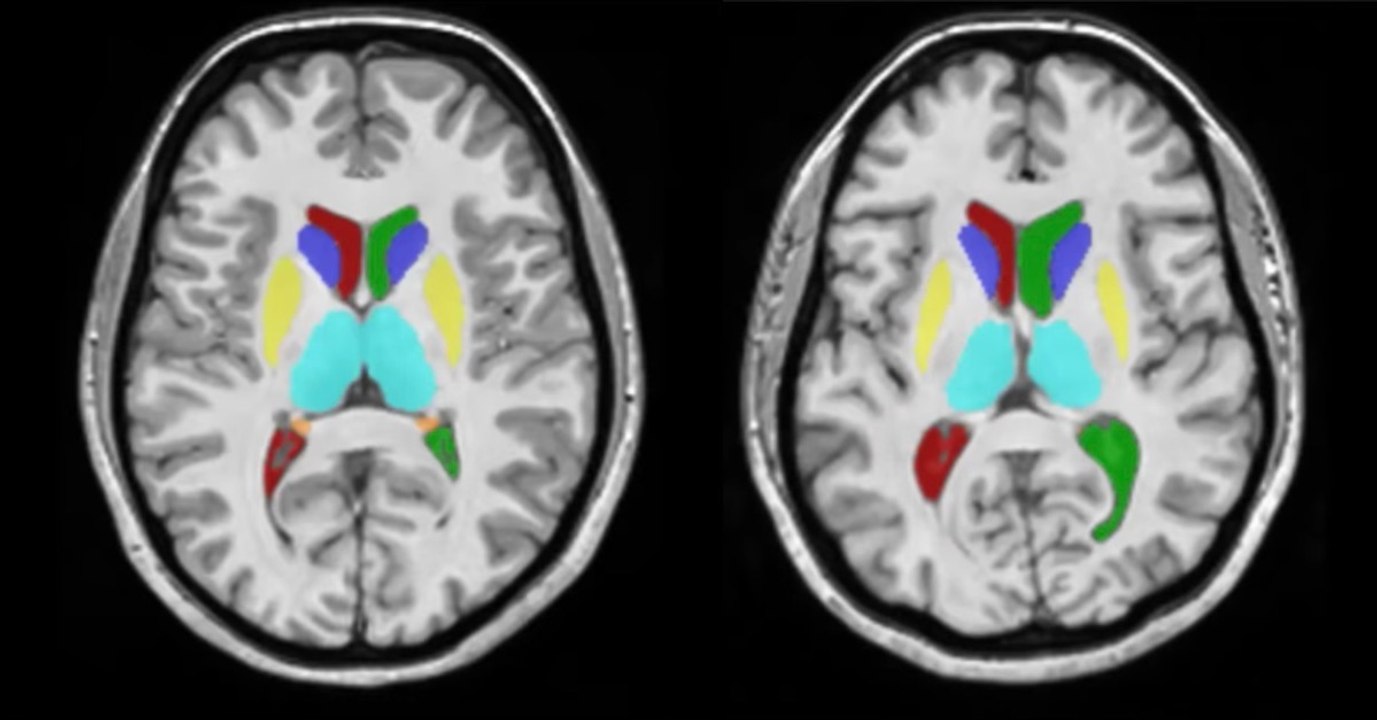

Des chercheurs dévoilent comment notre cerveau évolue au cours de notre vie 1:20

Des chercheurs dévoilent comment notre cerveau évolue a...

Gentside Savoir 52 views